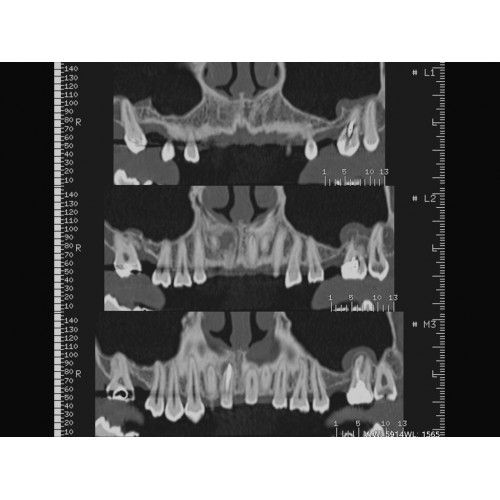

Неврологические исследования

• Выявление инсультов, опухолей головного мозга и травматических повреждений.

• Диагностика заболеваний позвоночника и межпозвоночных грыж.